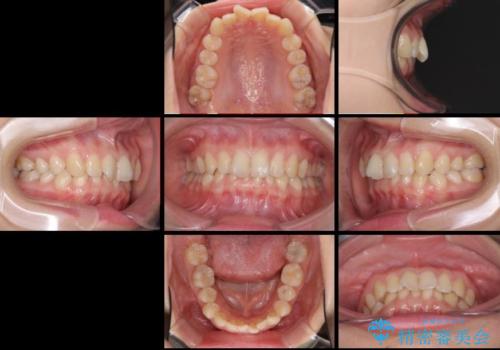

- 口元の深い咬み合わせ(ディープバイト)を気にして来院された患者様です。

インビザラインによる上下歯列の遠心移動(後方移動)により、口元のデコボコとディープバイトを改善することとしました。

下顎左右の犬歯とその後ろにある第一小臼歯、計4歯がシミュレーション通りに動かずディープバイトがなかなか改善されませんでした。

マウスピースの再製作を何度か行いましたがうまくいかないため、部分的にワイヤー矯正を併用することを提案しました。しかし、最も気になっていた前歯のデコボコはきれいに改善されたため、これ以上治療を希望されず、治療を終了することとしました。(今後気になった際には再開する予定です)